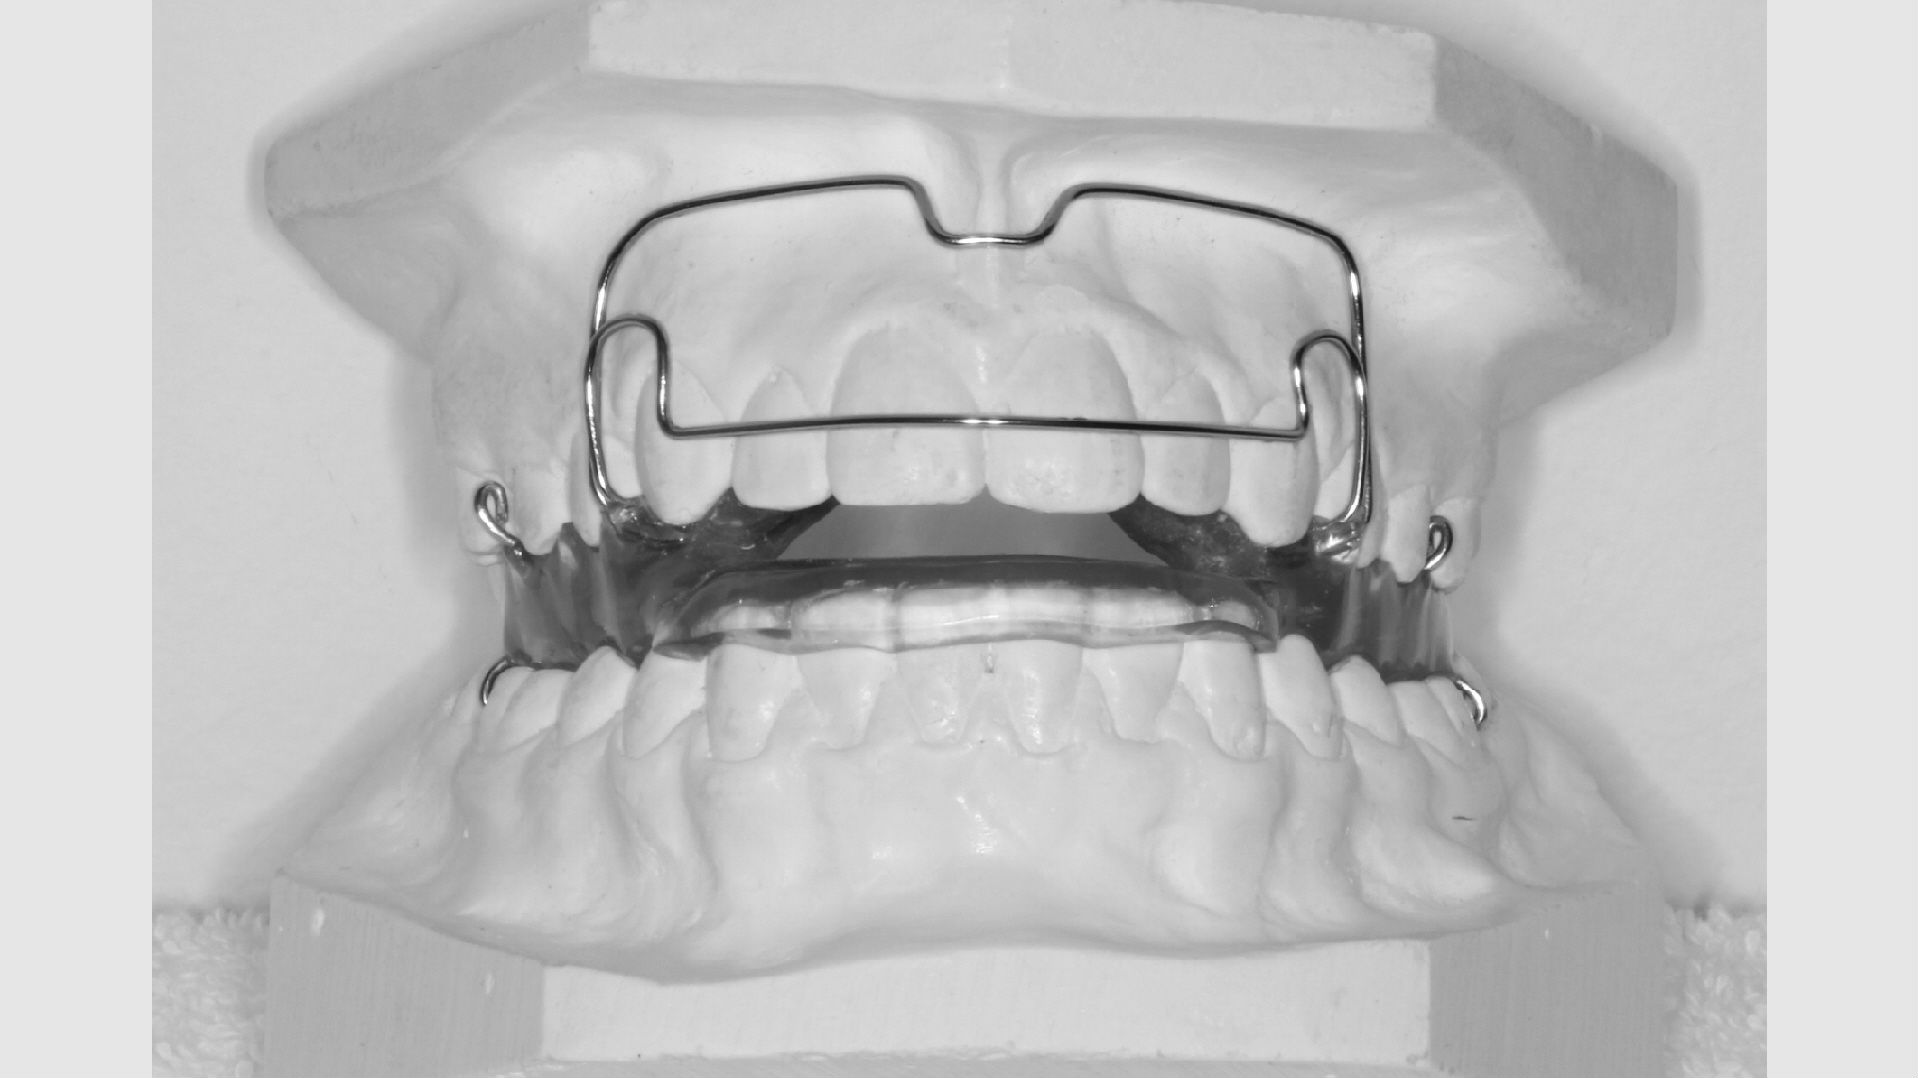

Hvis behandlingen skal gøres med en aftagelig bøjle, får dit barn eventuelt taget aftryk hertil umiddelbart efter samtalen.

Aftagelige bøjler

Nogle tandstillingsfejl kan rettes med bøjler, du selv kan tage ind og ud. For at de skal virke, er det naturligvis afgørende, at du bruger bøjlen på den rigtige måde. Ofte vil det være nødvendigt, at du har bøjlen på i alle døgnets 24 timer - på nær når du spiser og børster tænder. Du vil altid få klar besked om, hvordan og hvor meget du skal bruge din bøjle.

Den aftagelige bøjle skal holdes godt ren. Det gør du med en tandbørste og lidt flydende, uparfumeret sæbe og ikke for varmt vand. Bøjlen kan ikke tåle kogende vand og kan ikke gå i opvaskemaskinen.

Når du får din bøjle, får du også en æske til at opbevare den i, når den ikke er i munden. Det er vigtigt at have æsken med sig og bruge den konsekvent, så bøjlen ikke forsvinder. Har I hund, er det vigtigt at sørge for, at hunden ikke kan få fat i bøjlen.

Det tager i gennemsnit 2 år at få rettet tænder med fast bøjle, hvorefter du får nogle holdebøjler. Der limes ofte en tråd bag på fortænderne i over- og underkæbe. Derudover får du en skinne eller plade til at sove med hver nat i omkring to år efter, bøjlen er taget af. Disse holdebøjler er vigtige at bruge og holde ved lige, hvis man ønsker at bevare tænderne i deres nye position.